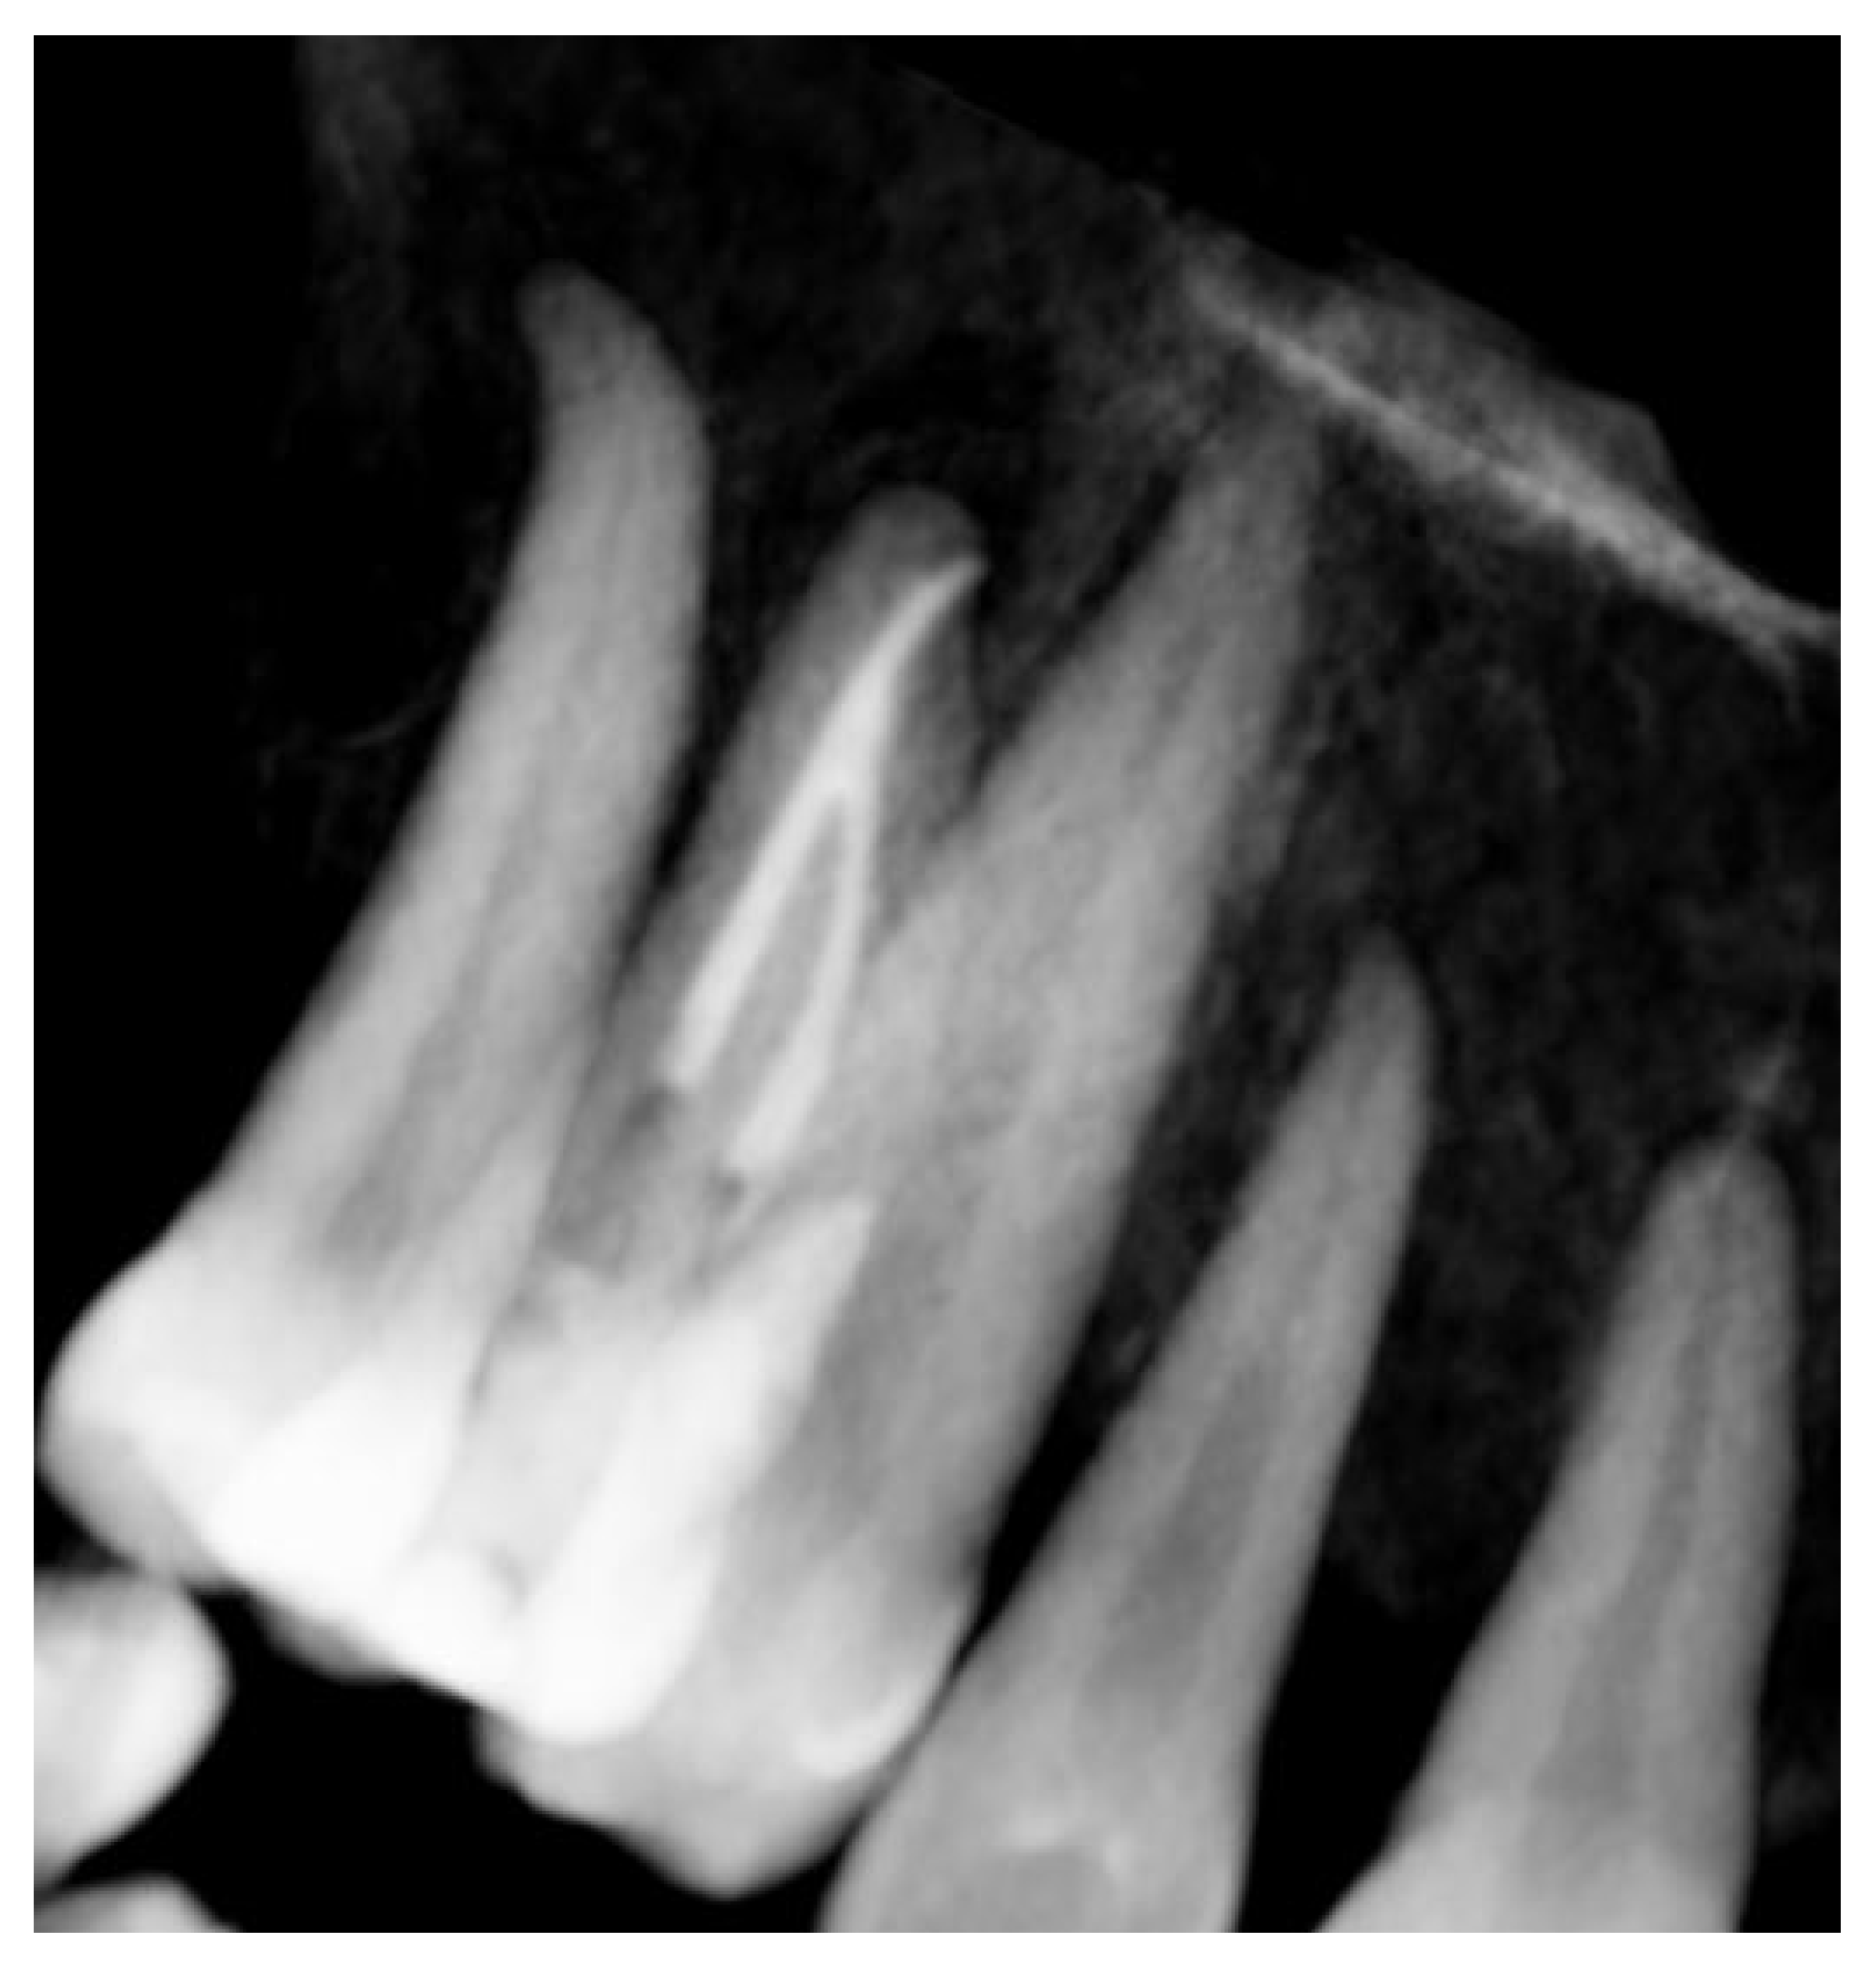

At the 12-month radiographic follow-up, healing of the EPL was confirmed. Restoration of the lamina dura and the periodontal ligament adjacent to the treated site was observed (Figure 16 and Figure 17).

Figure 16.

Intraoral radiography of tooth 1.4 at 12-month follow-up.

Figure 17.

EPL before (A) and after treatment (red circle showing mesiocervical widening of the lamina dura space) (B) and at 12-month follow-up (C) with radiographic evidence of restoration of the lamina dura (green circle), periodontal ligament space and absence of PL.